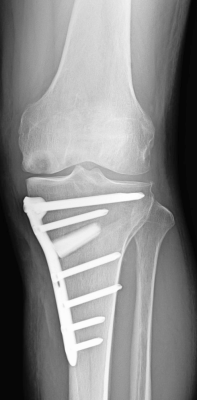

高位脛骨骨切り術術後

当科で行っている主な手術は、骨折全般、変形性膝関節症に対する人工膝関節置換術(全置換、単顆置換)や高位脛骨骨切り術、膝半月板損傷に対する関節鏡手術、変形性股関節症に対する人工股関節置換術、神経・腱・血管に対する微小外科を含む手外科手術、肩腱板断裂に対する修復術、変形性肩関節症に対するリバース型人工肩関節置換術などです。

なお、人工膝関節置換術においては、症例に応じてナビゲーションの使用やオーダーメイド人工膝関節(PSI=Patient Specific Instrument)を用いた手術を行っております。また、人工股関節置換術においては、筋肉や腱の損傷を最小限にする低侵襲アプローチによる手術を行っております。